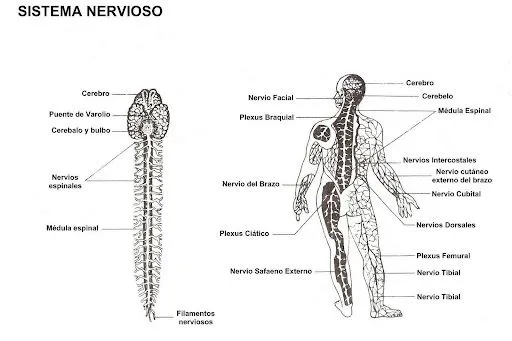

Dibujos del sistema nervioso central para colorear

Explora nuestra galería de dibujos del sistema nervioso central para colorear, ideales para aprender anatomía de forma didáctica y divertida.

Pix For > Sistema Nervioso Periferico Para Colorear

DIBUJOS DEL SISTEMA NERVIOSO CENTRAL PARA COLOREAR - Imagui

Sistema nervioso central y periferico para colorear - Imagui

Sistema nervioso central y periferico para colorear - Imagui